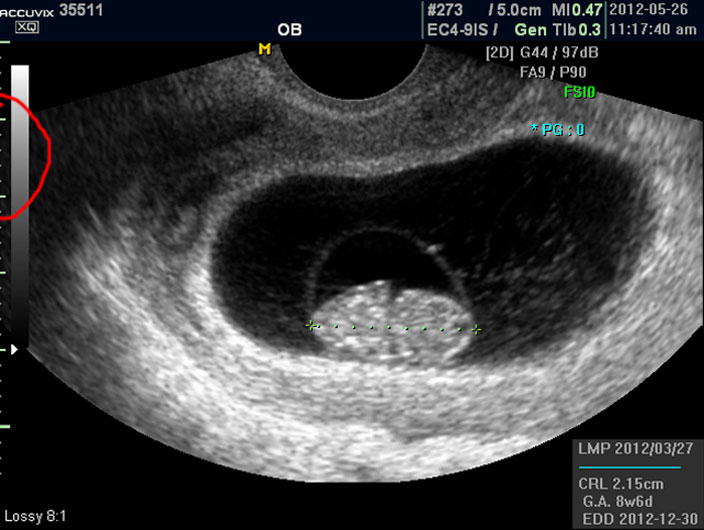

임신 8주 된 태아의 초음파 사진을 제대로 감상하는 방법을 설명드리겠습니다.

초음파 사진에서 살펴 볼 부분은 당연히 태아의 모습이겠지요.

그러나 임신 8주 정도의 초기에는 아직 아기가 쌀알 보다 조금 큰 정도이기 때문에 인간의 형체가 또렷하지는 않습니다.

그저 머리와 몸통 부분만 형성되어 있는 상태이지요.

우선 첫번째로 보이는 사진에서 가운데 하얗게 보이는 것이 태아입니다.

우측이 머리 부분이고 좌측이 몸통 부분이며 초기 임신에서는 아기 머리가 몸통의 반정도로 상당히 큰 상태입니다.

그리고 초음파 검사에서는 산전 초음파 이외의 다른 경우도 그렇지만 물에 가까운 성분일수록 검게 나오고 뼈처럼 단단해서 초음파 선이 투과하지 못하는 부분은 하얗게 나타납니다.

이는 투과 선은 다르지만 X 레이 검사 사진에서도 마찬가지입니다.

따라서 하얗게 보이는 태아 주변의 검은 부분은 양수입니다.

양수 바깥의 조금 회색으로 보이는 얼룩덜룩한 부분이 아기를 품고 있는 자궁이며 근종이나 기타 이상은 없는지 체크하지만 여기서는 산과 부분만 설명하기로 했기 때문에 따로 설명드리지 않습니다.